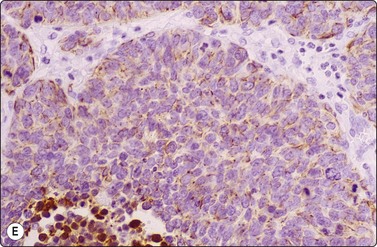

image image image

Fig. 8.28 High-grade neuroendocrine carcinoma; small cell carcinoma

(A, B) Smears showing ‘intermediate’ morphology. Loose aggregates of fragile cells with traumatization artifact and nuclear molding but some background cytoplasm (A, Pap, MP; B, H&E, HP). (C) Tissue section of resected peripheral stage 1 small cell carcinoma (H&E, HP).

image image image image image

Fig. 8.29 High-grade neuroendocrine carcinoma

Variable morphology including small cell and large cell patterns. (A) Low-power smear appearances of small cell carcinoma; (B) Higher-power examination shows some large cells with prominent nucleoli (A, H&E, LP; B, H&E, MP). (C,D) Tissue sections of resected peripheral stage 1 tumor showing areas of geographic necrosis and a predominance of large cells with prominent nucleoli (C, tissue section, H&E, LP, Inset, HP; D, tissue section, H&E, HP). (E) Positive immunostaining for chromogranin in resected specimen (E, tissue section, IPOX, HP).

Although ‘intermediate’ small cell carcinoma is no longer recognized as a separate category in international classifications, we find it a useful concept to highlight the occasional difficulty in distinguishing between small cell and poorly differentiated non-small cell carcinomas (Figs 8.28 and 8.29). There is overlap in nuclear size between small and large cell carcinomas and a tendency for inexperienced cytologists to include small cell carcinomas with larger than expected nuclei in the non-small cell category. In general, if the nuclear features of a problematical tumor are those of small cell carcinoma – that is, granular chromatin without prominent nucleoli – the neoplasm will usually fall into the small cell carcinoma group histologically, whereas vesicular nuclei with prominent nucleoli would generally be evidence of non-small cell tumor. However, large cell neuroendocrine carcinoma does provide special problems. Our experience is limited but is similar to Yang et al. who described various morphologic patterns in this family of tumors, including small cell-like and mixed small cell/large cell-like FNAC patterns.37 Cell size is therefore an important criterion and one to be critically evaluated. Tumors with nuclei larger than 2–3 times the diameter of a lymphocyte may be classified as LCNEC histologically, even if nuclear chromatin pattern and other cytological features are similar to those of small cell carcinoma (Fig. 8.29). Our approach is therefore to first come to a diagnosis of ‘high-grade neuroendocrine carcinoma’ and then to critically examine cell size and morphology to determine the best category – ‘small’ or ‘large’. We do, however, agree with the idea propounded by Marchevsky et al.89 that the distinction between the two categories may be somewhat artificial in view of the overlap in cell size between the two groups. This is an area which requires close cooperation with oncologists and an acceptance of the limitations of cytological diagnosis. It may be necessary to base management on clinical and staging findings in conjunction with inconclusive cytological tumor typing in some cases.

Our approach to problem cases has been to request more biopsy or cytological material for cell block and immunoperoxidase studies. Immunohistochemical demonstration of neuroendocrine differentiation using immunostaining for synaptophysin, chromogranin and CD56 reinforces a diagnosis of small cell carcinoma; however, some studies find up to 25% of small cell carcinomas are negative with all neuroendocrine markers.235 TTF-1 staining is usually seen in small cell carcinoma (>90% of cases) but is seldom seen in SCC. Strong positive nuclear p63 staining would favor a squamous lesion.213 A paranuclear CAM 5.2 keratin-positive dot similar to those seen in Merkel cell tumors and some other neuroendocrine tumors is a helpful criterion not seen in other poorly differentiated lung carcinomas. In ‘operable’ stage I tumors or peripheral tumors, very careful cytological assessment is necessary. Biopsy or lobectomy is advisable when diagnostic difficulty is not resolved by repeated FNB or FOB because some of these tumors will be large cell neuroendocrine carcinomas or atypical carcinoids, best treated by surgery (see Fig. 8.36).34